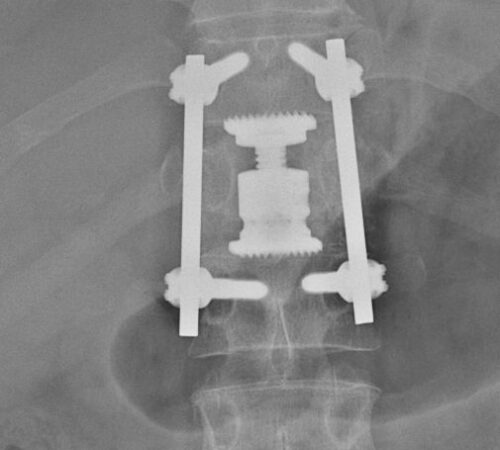

• Tříštivá zlomenina obratle T12 po kombinovaném ošetření vnitřním fixátorem v rozsahu T11-L1

Jednotlivé procedury se při operačním výkonu prolínají a fungují společně. Pro zajištění primární pooperační stability ze zadního přístupu používáme v krční i torakolumbální oblasti vnitřní fixátory. Jejich součástí jsou šrouby případně háky a spojovací tyče překlenující poraněný páteřní segment. Z předního přístupu jsou nejčastěji aplikovány kostní štěpy nebo klece přemostěné dlahou v krční oblasti, expandibilní klece a fixátory v torakolumbální oblasti. Všechny fixační prvky jsou vyrobeny ze slitiny titanu, která omezuje negativní stíny na vyšetření CT a jsou MR kompatibilní. Pro dosažení trvalé kostní stability používáme přemostění poraněného obratle nebo obratlů kostními štěpy z lopaty kosti kyčelní nebo syntetickou náhradu (trikalciumfosfát, hydroxiapatit).